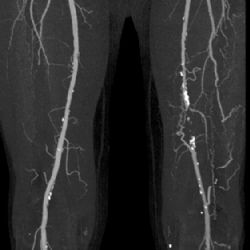

Ostrov: Nemocnice investovala 8 milionů do nového CT zařízení

Radiodiagnostické oddělení Nemocnice Ostrov od druhého pololetí letošního roku zprovoznilo nové moderní zařízení výpočetní tomografie CT. Celková výše investice se pohybuje okolo 8 milionů korun bez DPH.